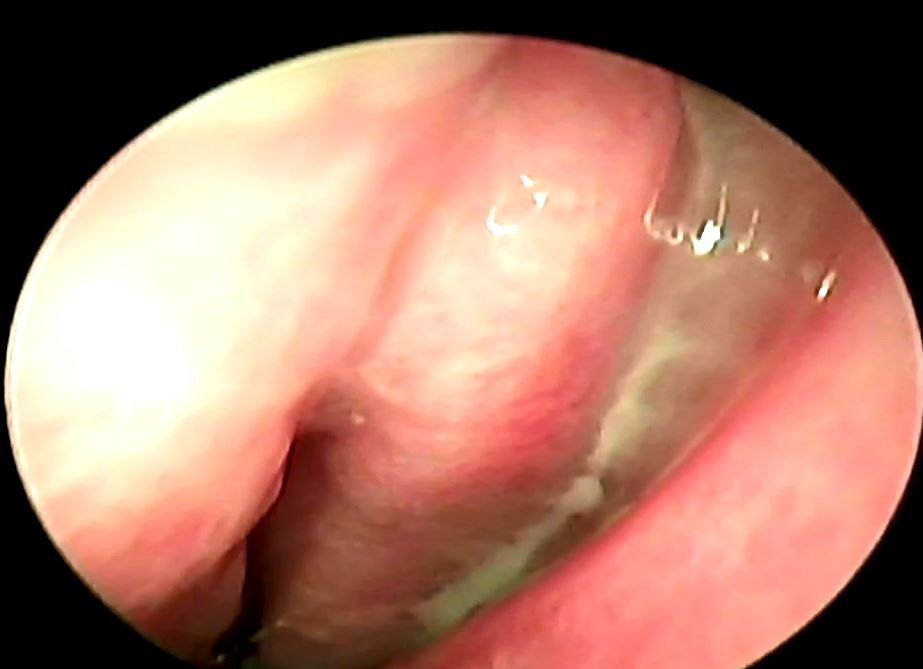

鼻竇是我們顱骨內的空腔,一般人通常會具有上頷竇、前篩竇、後篩竇、蝶竇、額竇等等,他們都跟我們的鼻腔有相通,所以通常鼻竇發炎的時候裡面的分泌物會跑到鼻腔中,導致病人會有膿鼻涕或是鼻涕倒流的症狀,一般來說鼻竇炎可以分為急性、亞急性或慢性,根據不同的感染原又可以分為細菌、病毒或是黴菌,其中最常見的是病毒性感染,每年在美國大約有3100人有得過鼻竇炎,是排名前五大可能會用到抗生素的疾病,當感染的時候鼻竇黏膜會腫脹導致鼻竇開口堵塞,同時病毒或細菌也會影響纖毛運動導致黏液排出困難進而堆積,所以就形成了更容易讓細菌或是病毒滋長的環境,一般來說超過10天以上都沒有任何進步的會高度懷疑是細菌性感染,或是一開始有進步又變嚴重了也會懷疑是細菌性感染,病毒感染通常是症狀治療,細菌性感染一般會給予抗生素,有時也會建議鼻內類固醇的使用以及鼻腔沖洗;一般鼻竇炎的診斷是依據病史以及理學檢查或室內視鏡檢查,不會常規使用影像學檢查除非是懷疑有併發症或是預計要手術治療的時候才會使用,影像學檢查無法判斷是細菌或是病毒性來源,至於細菌培養比較常用於懷疑有抗藥性的病人或是免疫不全的病人身上。

PS. 最後提一下抽鼻涕這件事,通常鼻竇炎的時候鼻涕很難擤乾淨,鼻膿裡面的蛋白質是很好的細菌培養皿,所以把深層的鼻涕抽掉有助於減少病菌的孳生,且抽完後鼻腔會通暢許多,這個治療比打任何針劑都還有效,如果能放輕鬆讓醫師幫您抽乾淨,相信對您的疾病是有幫助的!!